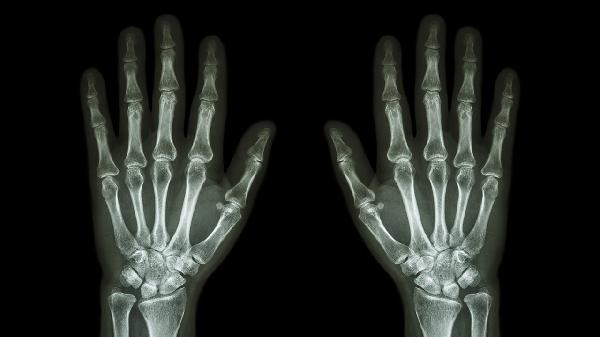

还可能是骨关节炎、类风湿性关节炎等原因引起的上述症状。建议患者及时到医院进一步检查,明确病因后及时治疗。治疗过程中注意清淡饮食,不要吃辛辣食物,以免加重症状。